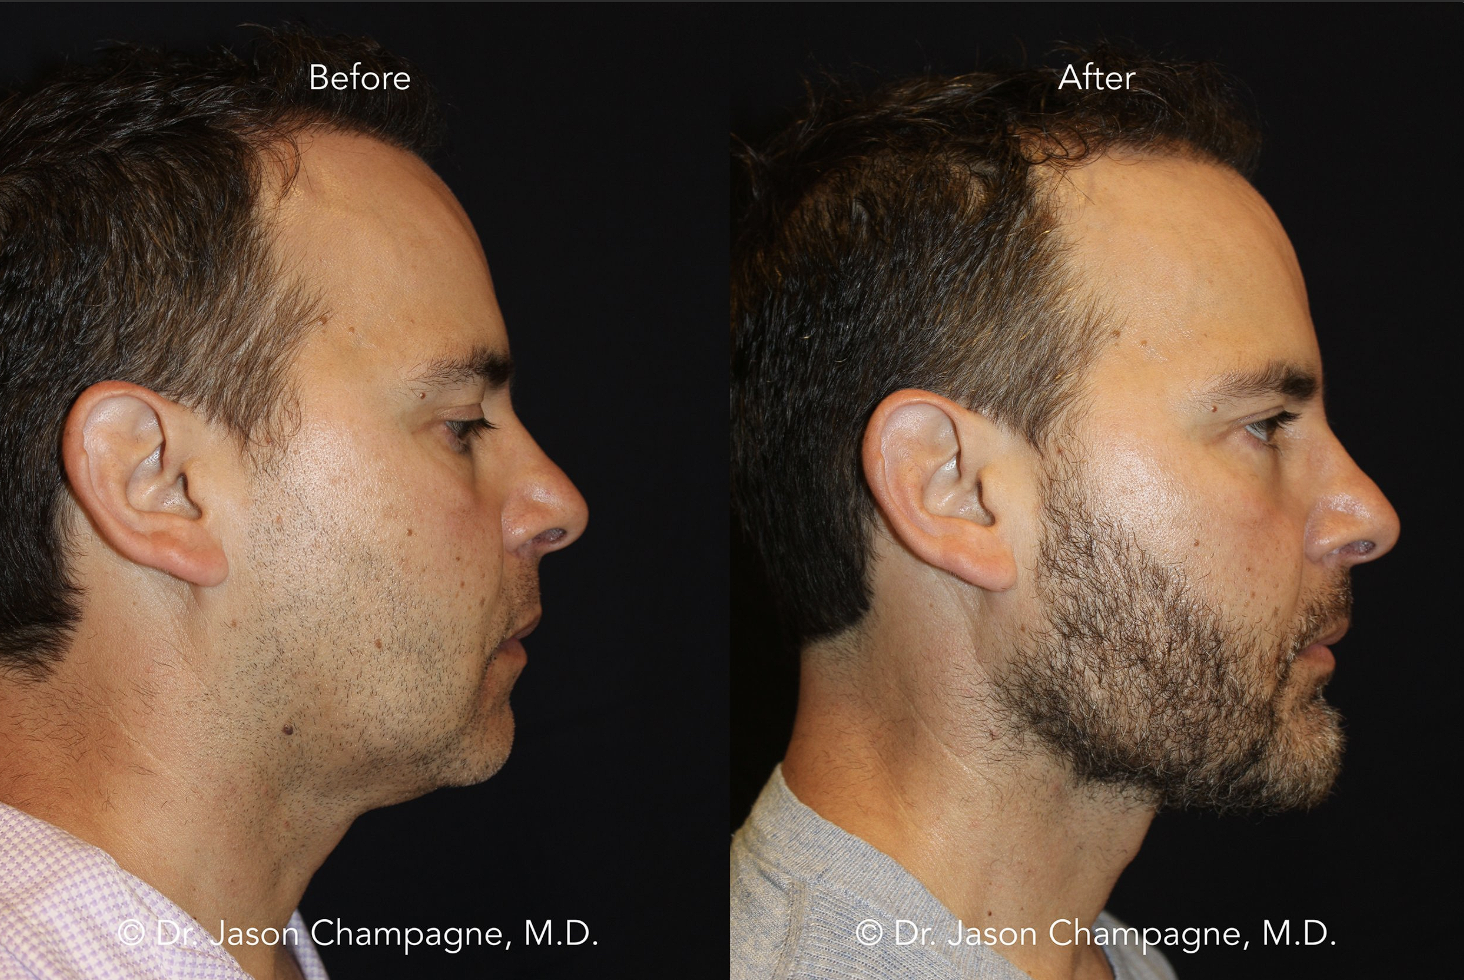

2-Genioplasty (Sliding Genio)

Genioplasty, çene ucunun konumunu ve şeklini düzeltir; mandibulanın kendisini değil. Bu yüzden alt çene gerideyse sorunu çözmez, sadece kamufle eder. En sık hata mandibular gerilik varken genioplasty ile işin çözülebileceğini sanmaktır.

Doğru vakada genioplasty etkilidir. Özellikle çene ucu projeksiyonu yetersiz ama mandibula konumu kabul edilebilir olan yüzlerde, profili belirgin şekilde toparlar. Vertikal ayarlamalar (uzatma veya kısaltma) da alt yüz oranlarını düzeltmede işe yarar.

Genioplasty, BSSO’nun alternatifi değildir. Çoğu vakada BSSO’dan sonra gerekmez; gerekiyorsa da küçük bir dengeleme amacıyla yapılır.

Attentionspancels: Genioplasty bir düzeltme değil, ayar ameliyatıdır. Doğru kemik üzerinde, doğru miktarda yapıldığında işe yarar; yanlış vakada ise sadece kamuflaj olur.

↓↓8mm genioplasty↓↓

↓↓10mm genioplasty↓↓

3- Asymmetric Mandibular Osteotomy

2-Genioplasty (Sliding Genio)

Genioplasty, çene ucunun konumunu ve şeklini düzeltir; mandibulanın kendisini değil. Bu yüzden alt çene gerideyse sorunu çözmez, sadece kamufle eder. En sık hata mandibular gerilik varken genioplasty ile işin çözülebileceğini sanmaktır.

Doğru vakada genioplasty etkilidir. Özellikle çene ucu projeksiyonu yetersiz ama mandibula konumu kabul edilebilir olan yüzlerde, profili belirgin şekilde toparlar. Vertikal ayarlamalar (uzatma veya kısaltma) da alt yüz oranlarını düzeltmede işe yarar.

Genioplasty, BSSO’nun alternatifi değildir. Çoğu vakada BSSO’dan sonra gerekmez; gerekiyorsa da küçük bir dengeleme amacıyla yapılır.

Attentionspancels: Genioplasty bir düzeltme değil, ayar ameliyatıdır. Doğru kemik üzerinde, doğru miktarda yapıldığında işe yarar; yanlış vakada ise sadece kamuflaj olur.

↓↓8mm genioplasty↓↓

↓↓10mm genioplasty↓↓